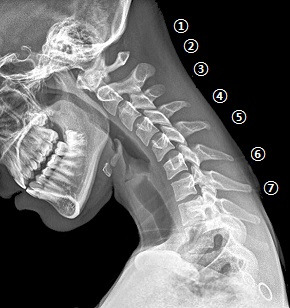

neck.png 가운데 손가락 끝을 목 뼈 뒤 돌기 옆에 마주 대고 고개를 뒤로 젖힌다

la-he-text-neck-20150404.jpg ⓛ번부터 ⑦번 경추까지 차례로 가운데 손가락을 대고 뒤로 젖힌다